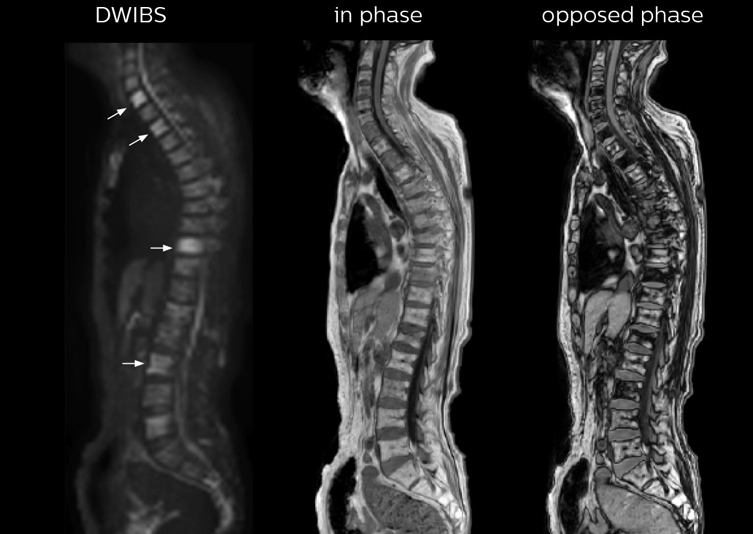

“mDIXON FFE allows us to quickly get information we need to assess the presence of fat. That gives us more information when we need to diagnose bone lesions, and when we are asked to judge fat-containing lesions such as hepatocellular or renal carcinoma,” Dr. Nobusawa says. “The mDIXON fat images can help us to differentiate fatty bone marrow from bone lesions. This is especially useful in elderly people, who tend to have fattier bone marrow. The water images provide a high signal-to-noise ratio in the intestinal canal, which is valuable for visualizing lesions in the colon,” he says.

Kawasaki Sawai Hospital’s whole body protocol also includes an mDIXON FFE sequence. Because mDIXON provides images for four contrast types – water only, fat only, in-phase and out-of-phase – from a single acquisition, it is useful in many ways.

“In-phase and out-phase sagittal T1-weighted FFE images help us to visualize and further characterize bone lesions such as metastasis and bone-marrow hyperplasia that have high signal on DWI. These images are also used throughout radiotherapy, to monitor changes in the fatty bone marrow.”